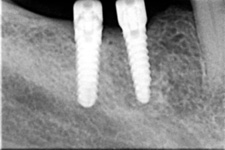

V případě chybění většího počtu zubů v postranních úsecích čelistí je možné ošetření pomocí implantátů, které nahradí ošetření pomocí snímacích náhrad kotvených na zbývajících zubech nebo patře.

Podmínkou je opět dostatečné množství kosti.

Protetické řešení může být pomocí můstku, který je kotvený na implantátech nebo pomocí jednotlivých korunek na implantátech.

V zásadě je možné do těchto můstků zařadit i přirozené zuby, zejména pokud je potřeba tyto zuby ošetřit proteticky

- korunkami. Korunky nebo můstky mohou být na implantáty nacementovány nebo přišroubovány.